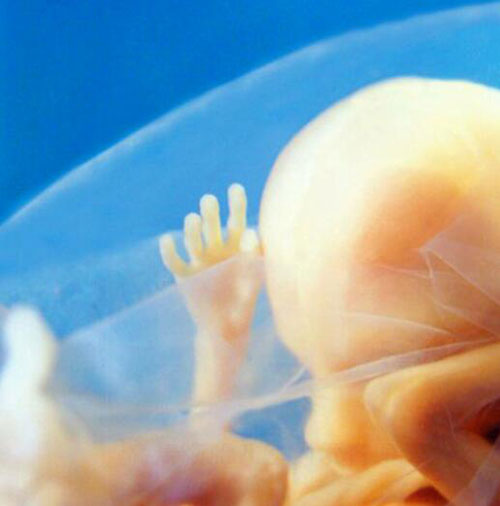

Những mạch máu ở bàn tay thai nhi rất rõ rệt vì thời điểm này, thai còn nhỏ, làn da mỏng. Tuy nhiên, các ngón tay đã đầy đủ bộ phận.

Hình chụp toàn thân một thai nhi chưa phát triển đầy đủ nhưng các bộ phận hình thù cơ bản đã khá rõ.